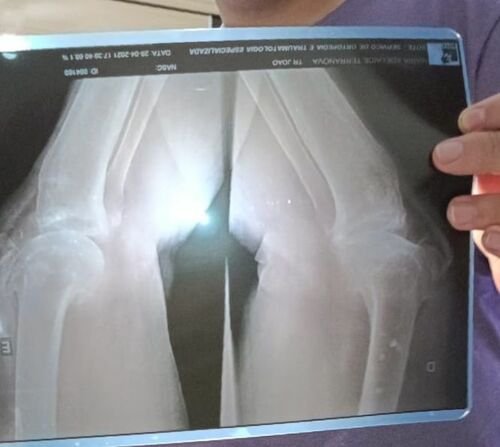

Eu sou Maria Adelaide terranova, tenho 70 anos e preciso contar com a ajuda de vocês. Relutei muito em aceitar essa sugestão dos amigos, mas o tempo está passando e não posso me dar mais ao luxo de esperar ganhar na mega sena, (rs) ou esperar o SUS liberar minha cirurgia ,considerando que as possibilidades são poucas ,pois moro em Juazeiro BA,interior da capital,o que dificulta ainda mais a realização desse procedimento cirúrgico ,porém preciso realizar com urgência .Estou cada vez mais limitada ,só ando em casa e com dificuldade,meus pés,joelhos estão inchados ,sinto dores fortíssimas .A minha locomoção está limitada porque meus joelhos estão desgastados , por conta da única profissão que tive na vida ,a qual fui e sou apaixonada até hoje .Essa profissão apaixonante foi ensinar danças ,especialmente ballet clássico ,jazz e um pouco de sapateado .Comecei aos 17 anos, dando aulas particulares em minha casa.Aos 22 anos ,comecei a ministrar aulas em Itabuna, com uma carga horária intensa, com muita garra e perseverança, consegui realizar o sonho de muitas meninas ,atendendo uma grande clientela,chegando a um total de 10 horas por dia, durante 20 anos. Tempos depois , aqui em Juazeiro, criei o Projeto " Nos Passos da Cidadania" projeto apoiado pelo Governo do Prefeito Joseph Bandeira,onde tínhamos quase 900 alunos em situação de risco e sem condições financeiras para pagar cursos extras de dança .Nada diminuía meu entusiasmo ,ministrava aulas com a mesma paixão, com o mesmo ritmo,para crianças e adolescentes. Assim,diante de uma vida ativa ,com constantes exercício físicos (na época com poucas proteções para os joelhos durante as aulas, pois, as salas não eram apropriadas para tal) ,tive desgastes nas Patelas ,junto com artrose nos dois(2) joelhos .No momento , estou correndo risco de ficar de cadeira de rodas,se não consegui fazer com urgência essa cirurgia nos dois joelhos. É um procedimento caro ,por conta da prótese, que além de importada é de reposição.O orçamento que o Hospital me passou na Sote de Juazeiro, foi de $84.000,00 cada joelho, totalizando $168.000,00(cento e sessenta e oito mil reais) . Gostaria de ressaltar que, pedi outro orçamento no hospital de Petrolina ,cidade vizinha,mas infelizmente,até o momento não me passaram ,esperando desde de fevereiro de 22 e não fui atendida .Diante do exposto ,vou tentar a ajuda de amigos e ex alunos e de todos que se sentirem tocados pela minha situação,para tentar fazer essas cirurgias.Desde de já, agradeço a colaboração de todos vocês.Qualquer valor será bem vindo,Deus abençoe grandemente a generosidade de todos